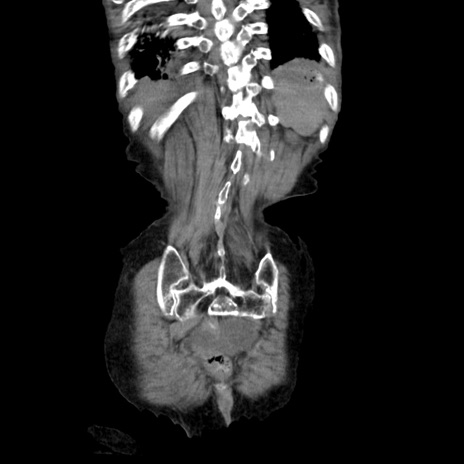

症例27(冠状断像)

【症例】80歳代女性

【主訴】嘔吐、腹痛

【現病歴】数時間前より嘔吐あり。心窩部痛出現し、徐々に右下腹痛あり。その後も数回嘔吐あり救急搬送となる。

【既往歴】左大腿骨頚部骨折手術

【身体所見】腹部は膨隆しているが軟らかく圧痛なし。腸雑音はやや亢進。

【データ】WBC 12000、CRP 19.05